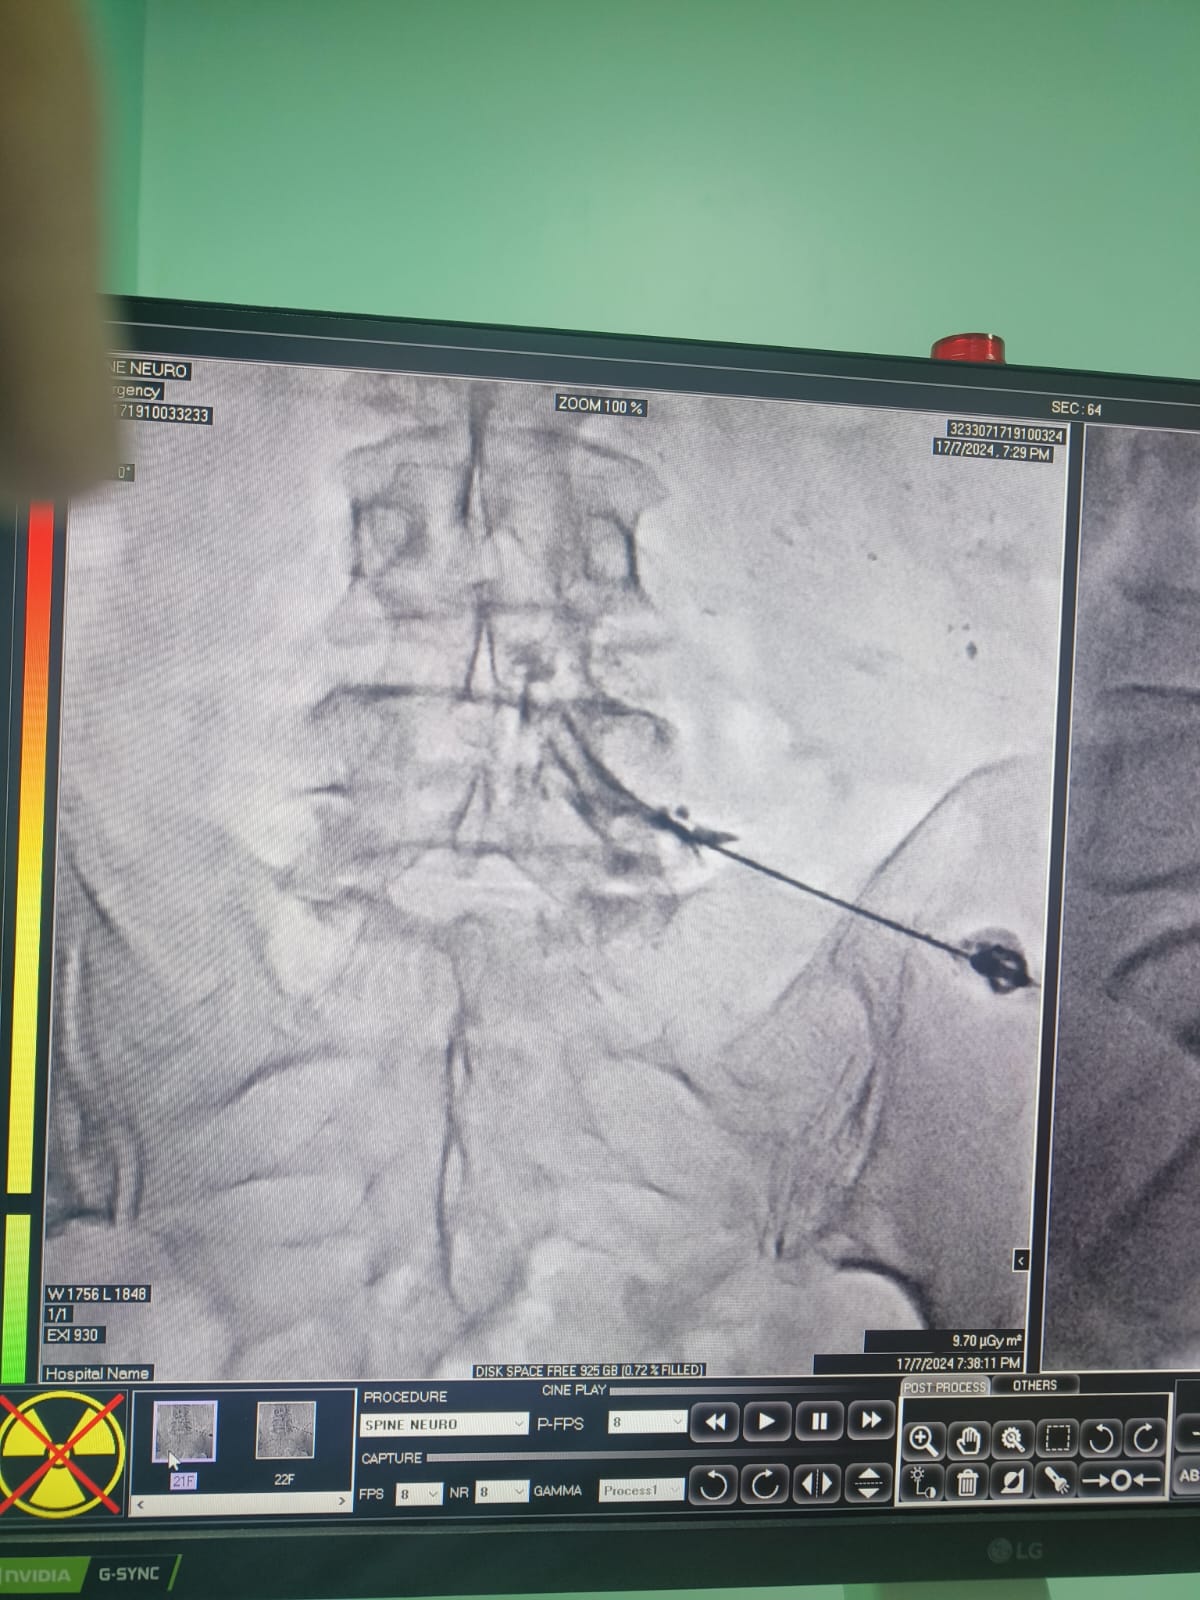

Vascular Neuro Intervention